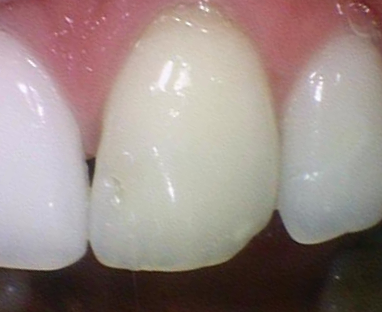

앞니의 경우 어금니 크라운보다 굉장한 정성이 소요됩니다.

보이는 부위이기 때문에 색도 주변 치아와 맞춰야하고,

모양도 정말 치아처럼 유사하게 만들어야 티가 거의 안나기 때문입니다.

특히 색이 문제인데, 치아가 그냥 하얀색이 아니라

자연치아 하나안에서도 쉐이드가 다양하기 때문에

옆 자연치아와 동일한 색,쉐이드로 맞추기가 굉장히 힘들기 때문입니다.

환자분이 최대한 색상 맞춰달라고, 모양도 최대한 대칭으로 해달라고 당부하셨는데

다행히 처음 끼워드린 크라운에 환자분이 색상이나 모양 매우 만족하셔서

크라운을 다시 수정보내는 일 없이 한번에 장착하였습니다.